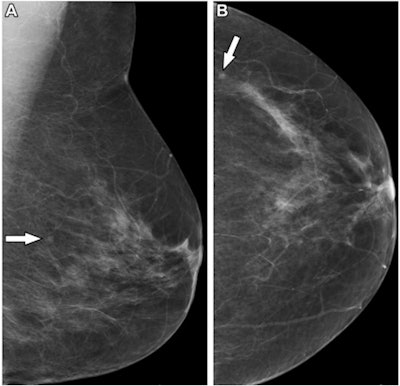

In countries with workforce constraints, could radiographers help with double reading of mammograms? British researchers believe they can, and say their results support the use of physician extenders for breast screening, according to a September 13 study in Radiology.

A team led by Yan Chen, PhD, from the University of Nottingham found no significant differences between radiologists and radiographers for cancer detection rate, recall rates, and positive predictive values.

They looked at data from 401 readers who double-read a total of 1,404,395 screening digital mammograms. The readers included 224 radiologists and 177 radiographers. The study authors measured cancer detection rate, recall rate, and positive predictive value, finding no statistically significant differences between the groups.